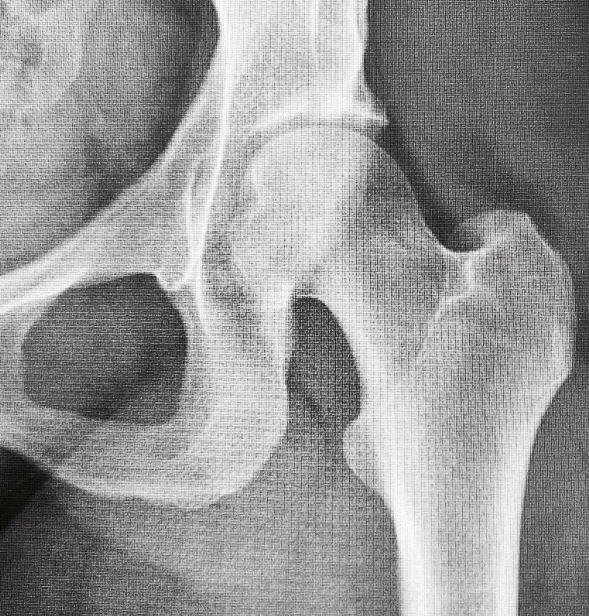

My hip has been gnarly. X-rays are negative, which is expected. Bone stress injuries are insidious in onset but can be detected with prompt imaging and rapid diagnosis. With my known low bone mineral density (2021 and 2022) despite playing ball sports growing up and with my stress fracture history, it’s a complete no brainer for an MRI. After going in circles with my PCP office, I sent a direct email to my PCP with my Coach’s assessment, instead of going through the call center which operates at a snail pace. The good news: Within the same hour, I had an order for an MRI. The bad news: The soonest available scanner time is 1 week away and in the middle of the night. The lesson: Keep advocating, keep being relentless, stay patient. Also, have brilliant people who will help you navigate the healthcare system.